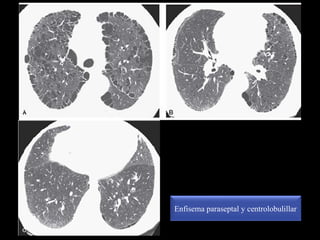

Enfisema centrolobulillar

Enfisema paraseptal y centrolobulillar